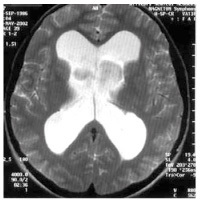

Quelle est la séquence de cette IRM? Quel diagnostic et pourquoi?

IRM séquence T2

HPN car dilatation tétra-ventriculaire, plage hyposignal T2 autour, et atrophie corticale modérée